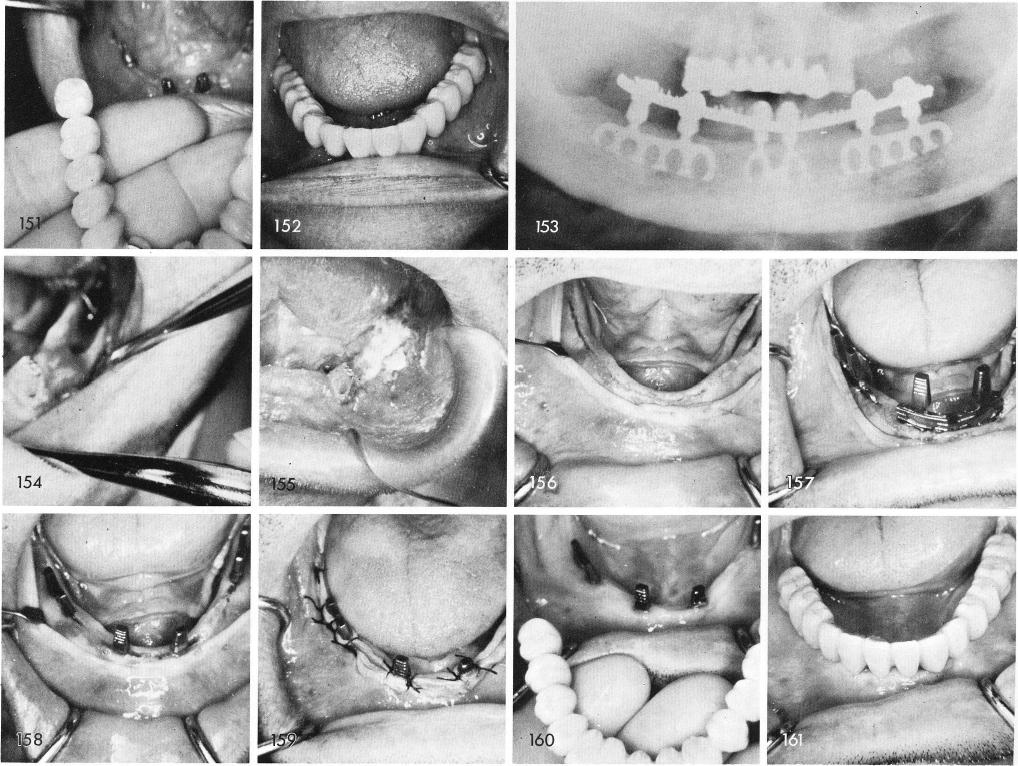

This next case shows what a failing blade, that was over-retained in the bone for a long period of time can do, fig. 154. The exact same situation occurred on the other side. Both blades were removed, plaster of paris was gently placed into the areas of bone loss and the remaining two teeth both severely periodontally involved were removed, fig. 155. The patient wore a conventional denture for nine months untill all the bone regenerated to nearly the same height as the buccal and lingual cortices of bone that flanked the original implant failure site. Nine months later the tissues were incised and reflected to expose the bone and grooves were made, fig. 156. Four blades were symmetrically inserted and tapped to proper positions, figs. 157, 158. Suturing was accomplished, fig. 159, and uneventful healing enabled the fixed bridge to be cemented into place with no complications, figs. 160, 161, 162. The post-operative x-ray, fig. 163.

1 Failing mandibular blade implant that was over-retained in the bone